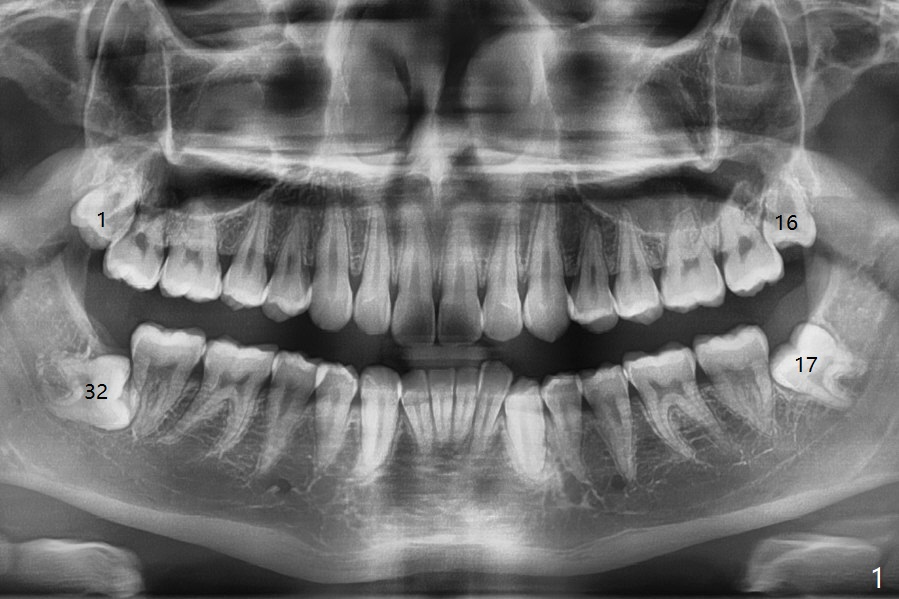

A 17-year-old man will return for extraction of 4 of the 3rd molars (Fig.1). Since the distobuccal surface of the tooth #31 may lack the bone (Fig.2 *), half of Augma will be placed in the distal portion of the sockets of #17 and 32, while allograft in the mesial one. Take PAs immediately post extraction to determine bony defects of the lower 3rd molars. Insert a piece of 2x2 gauze into the socket immediately post extraction. If hemorrhage is severe because of closeness between the mesial roots of the lower 3rd molars and the Inferior Alveolar Canal (Fig.2,3 red dashed line) after removal of the gauze, insert a half piece of Collagen Plug or more into the socket. If the latter is effective in hemostasis, Augma will be not applied, but allograft will be used, followed by Collagen Plug on the top of the allograft and sutures. Prepare both 4-0 and 5-0 ones. In fact the patient chooses to have 2 of the 3rd molars to be extracted. The extraction at #32 turns out to be extremely difficult with numerous sectioning because the crown of #32 is embedded into the distolingual surface of the fused conical roots of #31 (Fig.4,5). After insertion of a whole piece of Osteogen plug (Fig.7 O) into the root portion of the socket, Bond Apatite (1 cc) is pressed into the coronal portion of the socket (Fig.6 A). Due to oozing, the cement does not seem to be set completely. One third piece of Collagen plug is placed on the top of the cement before 4-0 Chromic gut suturing tightly. CBCT will be taken for better treatment approach prior to #17 extraction. Return to Plug Augma Xin Wei, DDS, PhD, MS 1st edition 10/06/2019, last revision 12/28/2019